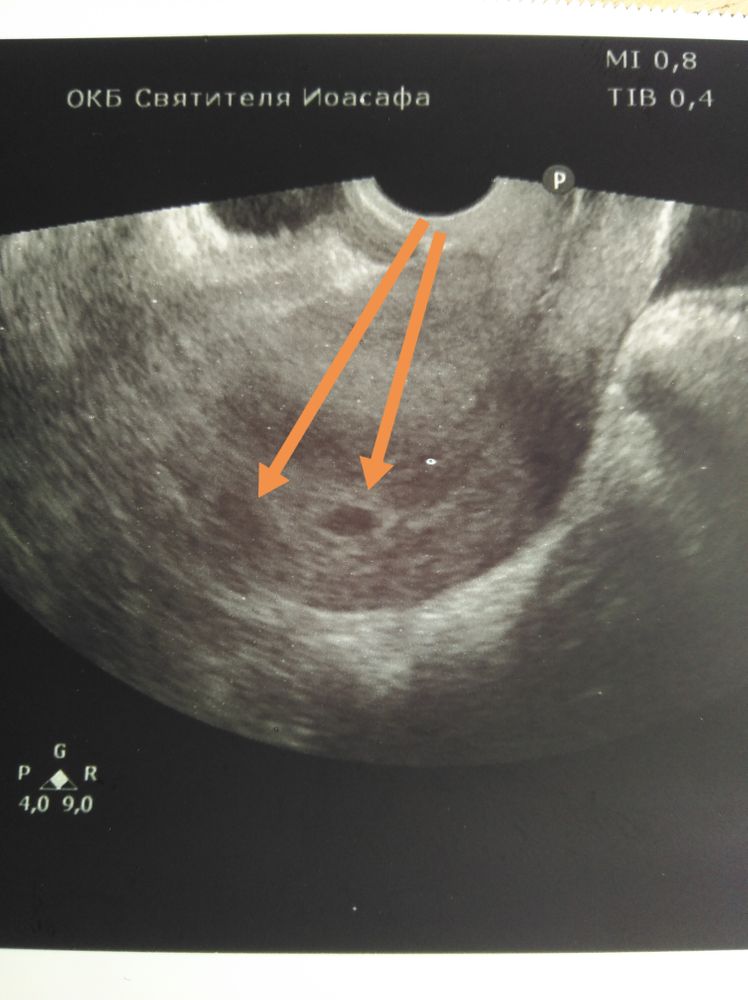

21 дпп побывала баба на узи. Моя ре свалила в отпуск, я конечно в печали, что рыба моя меня покинула, делала узи мне не особо опытная ре. За 2 секунды узи выяснилось, что есть ПЯ 10 мм одно, может 2, но это не точно, но точно есть 1😂😂😂 ЖМ не разглядывали, и вообще все рано, приходите через 2 недели, разберемся... Ну и погадаем на узи, кто сколько видит (узи отвратного качества)

Типо два, но одно точно😂😂 А переносили сколько? Вот мое узи с 2- мя пя на 18 дпп

Kate Agaeva, вот теперь понять бы что это за черная хера блуда в матке, рядом с эмбрионом

Kate Agaeva, так сколько ты видишь штук? я вроде 1, а если присмотреться 2...но он какой-то большой, чтож лошадь в 10 мм ре не разглядела?

Шепокляк_, я вижу реально одно то что можно принять за ПЯ

для дилетантов типа меня еще бы матку обвести.

Увидела у Вас долгожданный кружочек🥰Поздравляю😘растите, крепчайте!)

Вижу два 🤷🏻♀️ растите здоровенькими самое главное

Если прям по стрелкам смотреть, то вроде два. Ждём второе УЗИ разгадку🤞

Я вижу два и вижу даже желточные мешочки😁